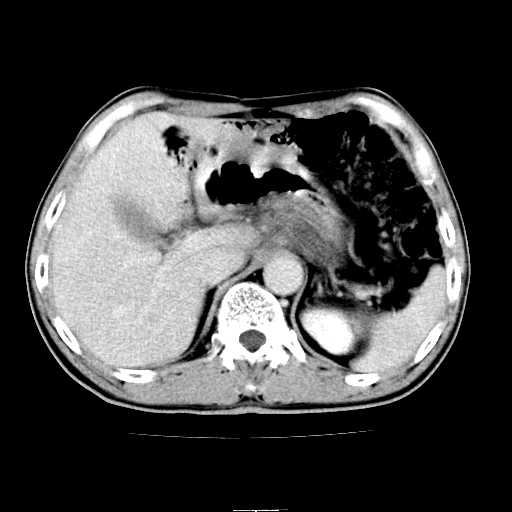

患者男,64岁,胃癌术后三个月,无明显不适。请讨论一下胰头前方小圆形低密度影为淋巴结还是肠管?

增强第6幅图上有气液平相通,是肠管,右肾低密度灶形态不规则似有壁结节,不除外转移.

应该考虑是肠管,理由1、平扫和增强对比,形态和内部的密度有明显改变。2、增强图片可见明显气液平面。

是肠管影,肠壁有强化。

是肠管影。还有右侧肾盂旁囊肿。

胰头右侧低密度影卡考虑为肠管;胰头前部低密度影,增强环形强化,结合临床首先考虑转移灶,其次考虑淋巴结结核(中心干酪性坏死)。

如是转移灶强化多为均质强化。如是结核应见到完整的壁且壁略厚。如是转移虽壁可不完整但内壁应该不规则。所以不支持是结核或转移。敬请指正!